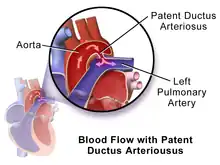

Differential cyanosis

Differential cyanosis is the bluish coloration of the lower but not the upper extremity and the head.[6] This is seen in patients with a patent ductus arteriosus.[6] Patients with a large ductus develop progressive pulmonary vascular disease, and pressure overload of the right ventricle occurs.[9] As soon as pulmonary pressure exceeds aortic pressure, shunt reversal (right-to-left shunt) occurs.[9] The upper extremity remains pink because deoxygenated blood flows through the patent duct and directly into the descending aorta while sparing the brachiocephalic trunk, left common carotid, and left subclavian arteries.